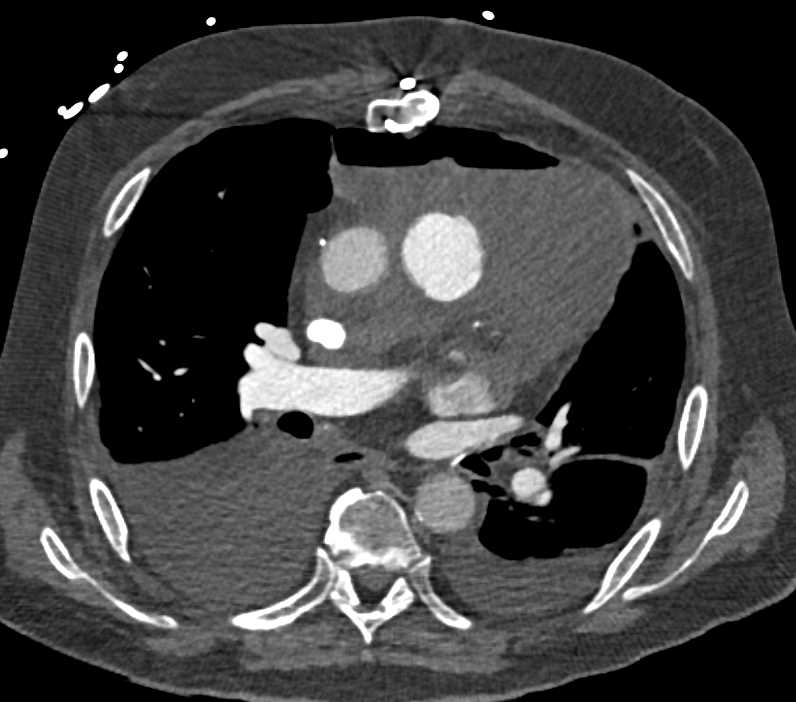

Post Cardiac Surgery Changes